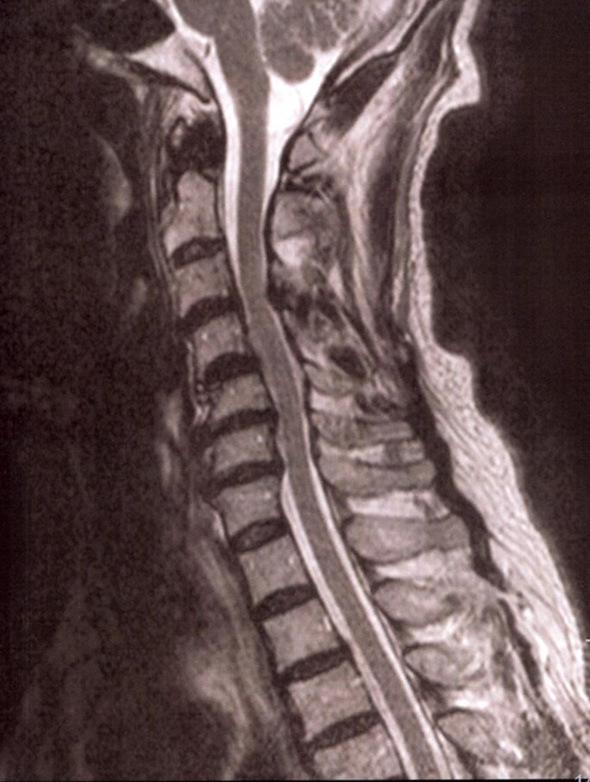

A 73-year-old man presented with muscle weakness and atrophy of his right arm. Atrophy of his left brachia and left calf had occurred 13 years before without any improvement or deterioration. His sister and cousin had a history of paralytic poliomyelitis. Serum poliovirus type 2 neutralizing antibody was elevated to 128×. Electromyography revealed chronic denervation potentials not only in the muscles affected previously but also in the unaffected muscles. Acute and chronic denervation potentials were found in the newly affected muscle. Postpolio syndrome should be considered in patients with unilateral muscular atrophy even when they have no history of paralytic poliomyelitis.

一位 73 岁男性出现右臂肌无力和萎缩。13 年前,他的左臂和左小腿也出现了萎缩,但没有任何改善或恶化。他的姐姐和表弟曾患有麻痹性脊髓灰质炎。血清肠道病毒 2 型中和抗体升高至 128×。肌电图显示,不仅在先前受累的肌肉中,而且在未受累的肌肉中也存在慢性去神经电位。新受累的肌肉中也发现了急性和慢性去神经电位。即使患者没有麻痹性脊髓灰质炎病史,单侧肌肉萎缩的患者也应考虑患有脊髓灰质炎后综合征。